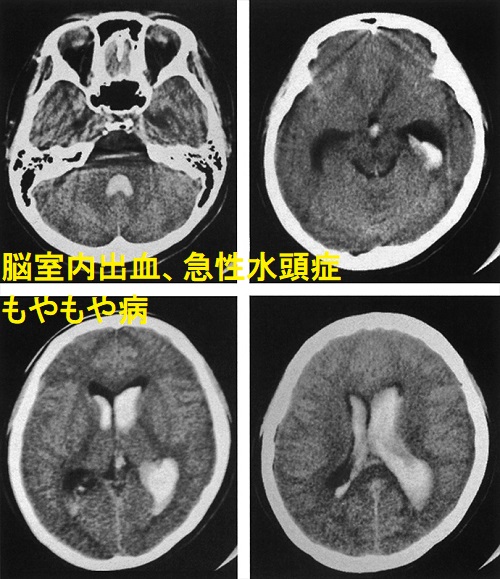

- 脳出血、くも膜下出血、脳室内出血と急性水頭症

甲状腺機能亢進症/バセドウ病など基礎疾患がある場合、「類もやもや病」と言われ、甲状腺治療開始後に脳虚血症状も改善する報告が多くあります。状況によっては(改善が見込めない場合)、甲状腺機能改善後に脳神経外科で脳血行再建術を行う事になります。

もやもや病(ウィリス動脈輪閉塞症)では甲状腺自己免疫抗体の陽性率が高いとされ、共通の自己免疫が考えられます。

もやもや病(ウィリス動脈輪閉塞症)の約50%で甲状腺自己抗体[抗甲状腺ペルオキシダーゼ抗体(TPO抗体)、抗サイログロブリン抗体(Tg抗体)、TBII(第一世代のバセドウ病抗体)]が認められる(対照群20.0%)(Stroke. 2010 Jan;41(1):173-6.)

もやもや病(ウィリス動脈輪閉塞症)の甲状腺機能亢進症、潜在性甲状腺機能亢進症、潜在性甲状腺機能低下症患者の比率、および抗甲状腺ペルオキシダーゼ抗体(TPO抗体)・抗サイログロブリン抗体(Tg抗体)の陽性率は、健常対照群より有意に高い(Stroke. 2011 Apr;42(4):1138-9.)。